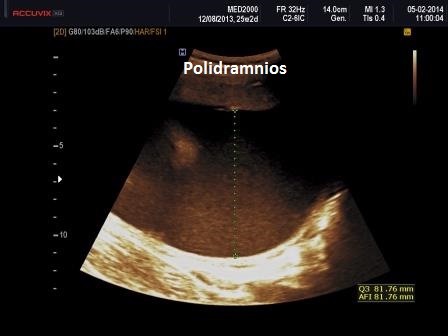

3. polidramnios